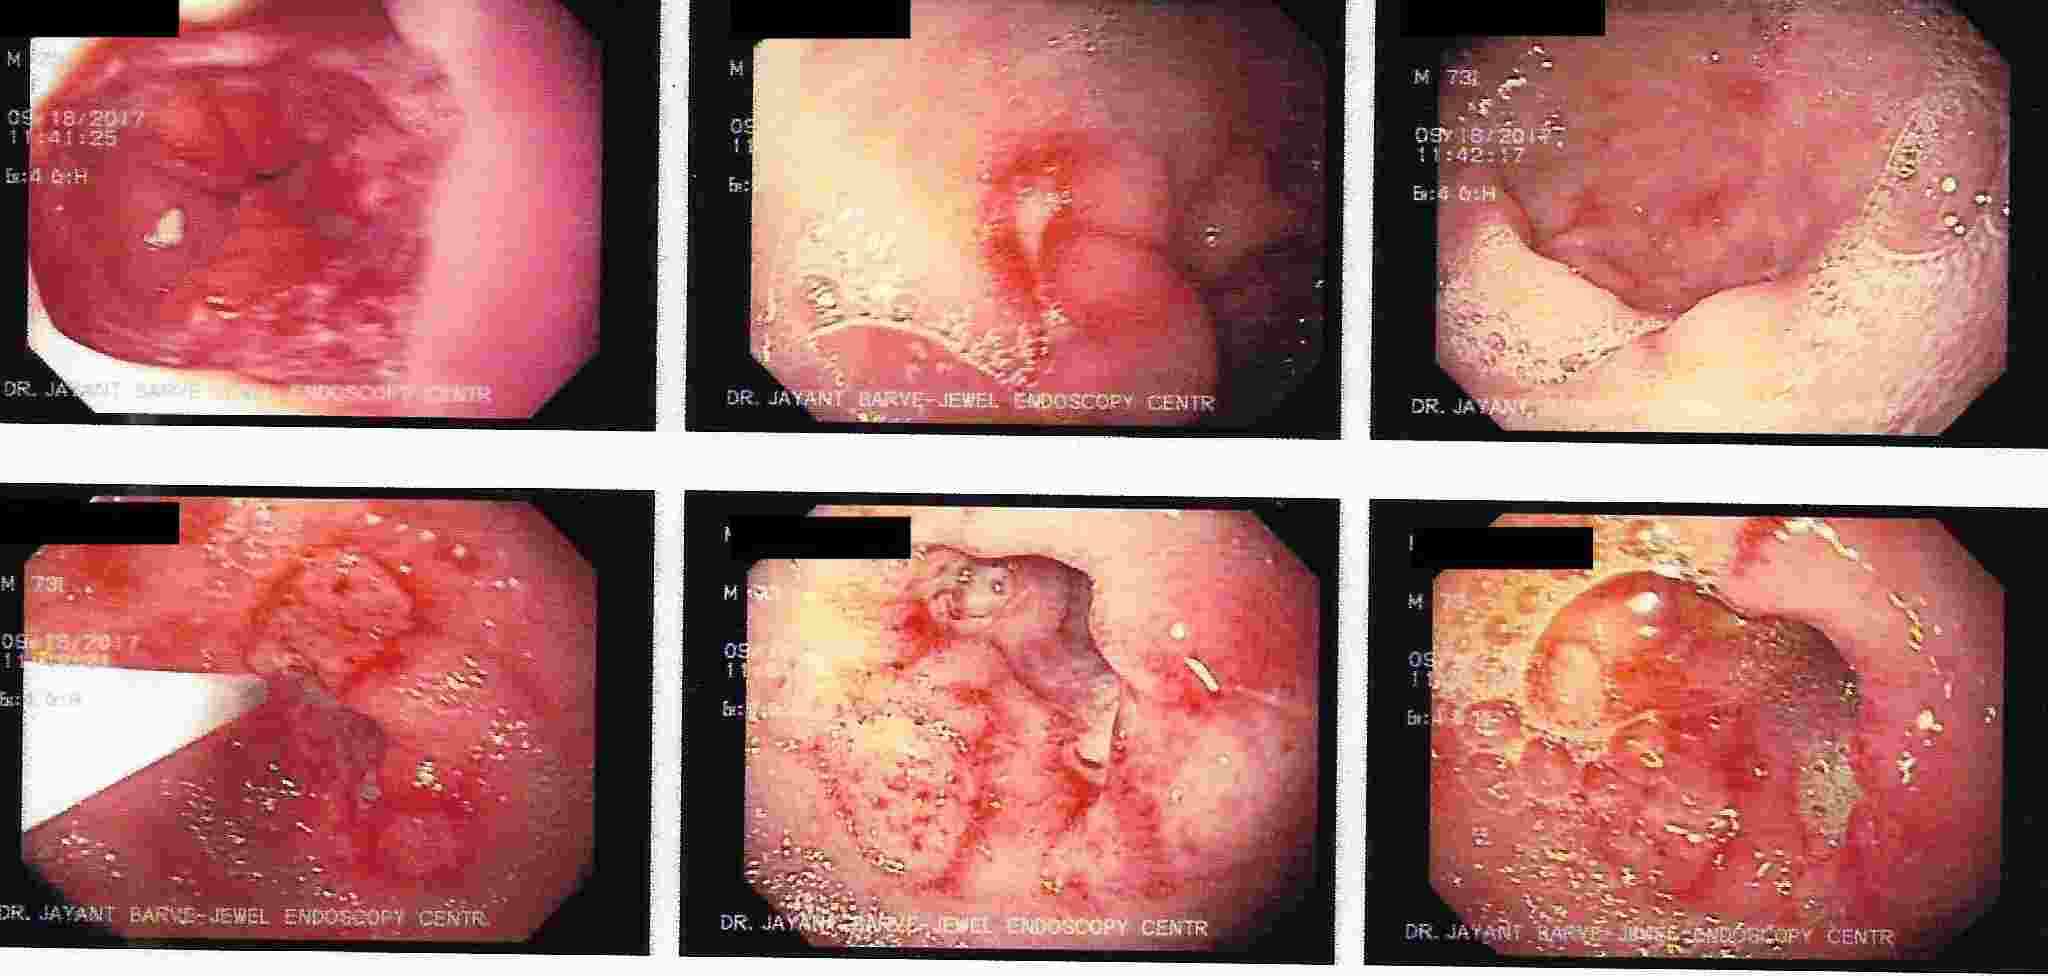

A revolution happened in gastroenterology 50 years ago due to invention of flexible endoscope.

For the first time gastroenterologist had an opportunity to visualise the digestive tract live and

make a diagnosis with very high accuracy. Subsequent developments resulted in invention of videoscopes with

its digital advantage and allowed treatment of many diseases of digestive tract without any surgical intervention,

hospitalisation, minimum morbidity and mortality and a cheaper option of treatment.

It allowed early diagnosis of cancer

and its endoscopic treatment without need for surgery.

GASTROINTESTINAL ENDOSCOPY

Gastrointestinal endoscopy (visualization of digestive tract)

is broadly divided into following categories :

A. UPPER GI ENDOSCOPY popularly known as GASTROSCOPY.

This is done commonly as an out patient procedure with mild sedation without anaesthesia.

Patient can resume with daily routine within an hour.

But should not drive for 2 hours if patient has received sedation.

This procedure allows diagnosis of diseases of upper Gastrointestinal tract, esophagus, stomach and duodenum.